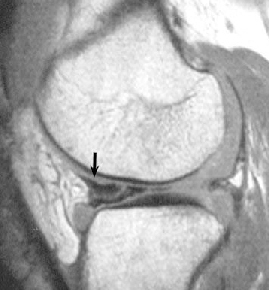

• ACL 손상 방사선 사진1